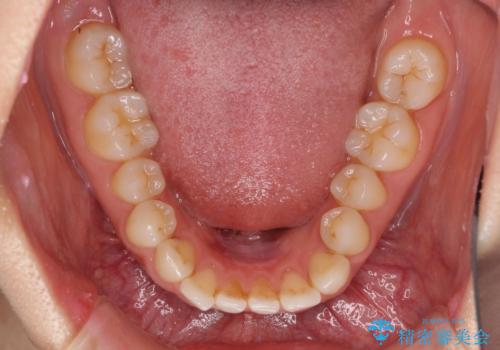

欠損歯と矮小歯 矯正治療と前歯のセラミック治療

- 前歯の隙間を気にして来院された患者様です。

診察の結果、前歯が1本欠損しており、さらに矮小歯(通常よりも小さい歯)が1本存在していました。

欠損による前歯のスペースが大きかったため、事前にワイヤー矯正で前歯の位置を大きく動かし、その後は上下をインビザラインで整えることとしました。

矯正治療後には欠損部はオールセラミックブリッジに、矮小歯はオールセラミッククラウンにて補綴することとしました。